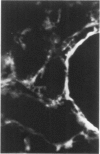

Antisera to human uterine actomyosin were prepared in rabbits and conjugated with fluorescein (F-AUAM). When F-AUAM was applied to frozen sections of normal human kidney which were then examined by ultraviolet light microscopy, it was observed that vascular smooth muscle, endothelium of arteries, veins, and peritubular capillaries and glomerular mesangial cells were immunofluorescent. Neither glomerular endothelium nor epithelial cells of Bowman's capsule or renal tubules were stained by F-AUAM. The specificity of antisera for actomyosin was confirmed by absorption and blocking studies, examination of a wide variety of tissues and immunodiffusion in agarose gel. It may be inferred from these data that mesangial cells are contractile. Contraction of the mesangium may play a significant role in regulating glomerular blood flow and in the reaction of the glomerulus to injury.

Images in this article